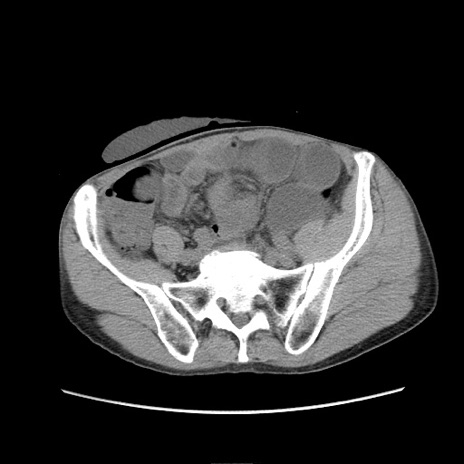

症例11(横断像)

冠状断像

【症例】 60歳代男性

【主訴】 下腹部痛

【現病歴】 本日夜中より下腹部痛の症状認め、受診。

【既往歴】 膀胱癌(膀胱全摘+尿管皮膚瘻術) 、胃癌術後

【身体所見】 BT 35.3℃、PR 58/min、BP 136/98mHg、腹部平坦、軟、腸蠕動音±、ストマ留置あり、左上腹部~正中部に圧痛あり、反跳痛なし。

【データ】WBC 5100、CRP0.01